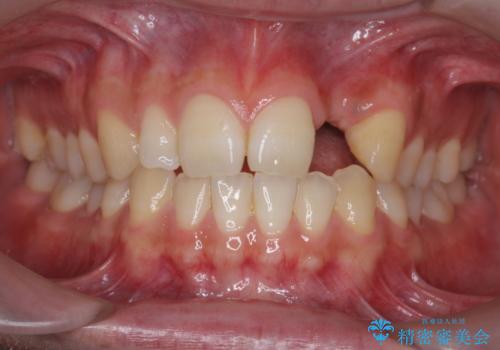

前歯部 インプラント治療

- 前歯の永久歯が元々なく、乳歯を失ったタイミングで前歯の審美性の回復を求めて来院されました。

機能・審美性の回復手段として、インプラント治療・ブリッジ・部分床義歯が考えられます。

それぞれの治療に特徴がありますが、取り外しの必要がなく隣の歯を削る必要も必要ないインプラント治療を選択されました。

前歯部にインプラントを埋入し、きれいに仕上げるためには骨の造成技術や歯肉の厚みを増すような処置を行い、インプラント周囲の環境を整備することが肝要です。